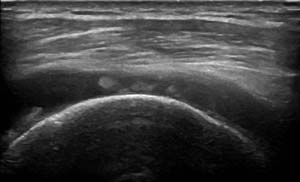

Ultraschalldiagnostik

Die Sonographie des Bewegungsapparates dient der bildlichen Darstellung von Muskeln, Sehnen, Bändern und Gelenken und stellt oftmals eine sinnvolle Ergänzung der Röntgendiagnostik dar.

Aufgrund der Tatsache, dass Beschwerden oftmals nicht durch Gelenke selbst hervorgerufen werden, sondern durch Veränderungen der umgebenden Weichteilstrukturen, ergänzt die Ultraschalluntersuchung als strahlenfreies Schnittbildverfahren die orthopädische Untersuchung.

Erkrankungen wie Muskelfaserrisse, Sehnenreizungen, Schleimbeutelentzündungen oder Gelenkergüsse können somit dignostiziert, im Verlauf beurteilt und spezifisch behandelt werden.